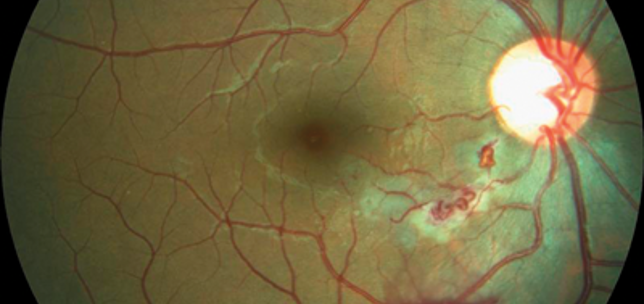

Retinal arteriovenous malformation

Alexandr Stepanov

·

1st June 2018

Education

Case Reports